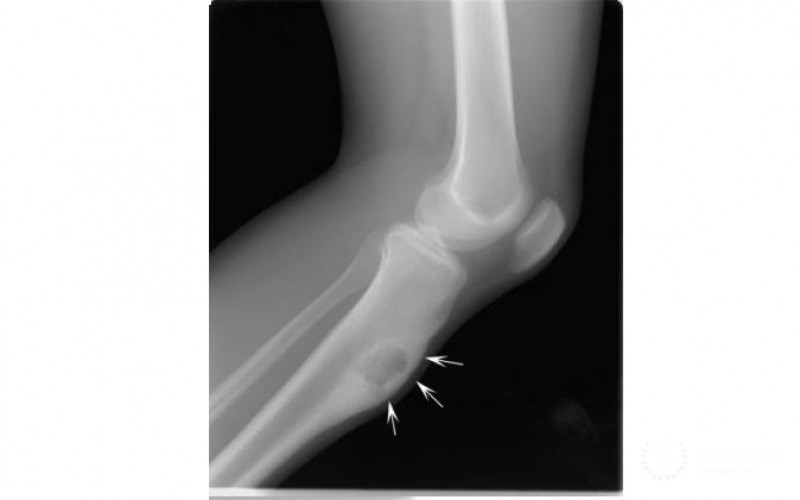

- Рентгенография;